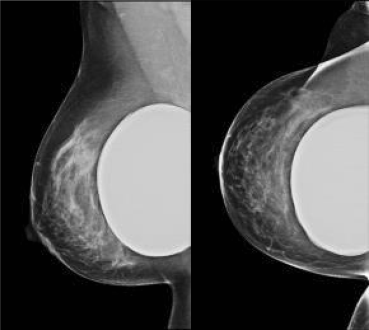

Prothesen

Vrouwen met siliconenprothesen tussen 50 en 75 jaar hebben recht op deelname aan het BOB. Er is geen verhoogd risico op het ontstaan van lekkage als gevolg van compressie tijdens de mammografie, de laboranten passen de compressie erop aan (fig. 3). Als de prothese echter zo groot is, dat hierdoor 70 % of meer mammaweefsel onzichtbaar wordt (het BOB heeft hiervoor een formule ontwikkeld), dan wordt de vrouw verwezen naar de afdeling Radiologie van het ziekenhuis. Van de radioloog en de laborant aldaar wordt verwacht, dat zij zich inspannen om speciale opnamen te maken, waarbij de prothese wordt weggedrukt, zodat er meer klierweefsel in beeld komt. Ze kunnen ook besluiten tot screening met echografie. Omdat het klierweefsel meer uitgespreid ligt over de prothese, zijn de resultaten hiervan relatief goed. Screening met MRI wordt niet aanbevolen [11].

Bij symptomatologie wordt (boven de 30 jaar) ook altijd eerst een mammografie verricht, aangevuld met echografie.

Figuur 3

Mammografie rechts van een vrouw met een retroglandulaire mammaprothese. Dit mammogram kan als goed beoordeelbaar worden beschouwd en toont geen afwijkingen. In verband met de aanwezigheid van de prothese wordt dit mammogram verslagen als BI-RADS 2 (benigne).